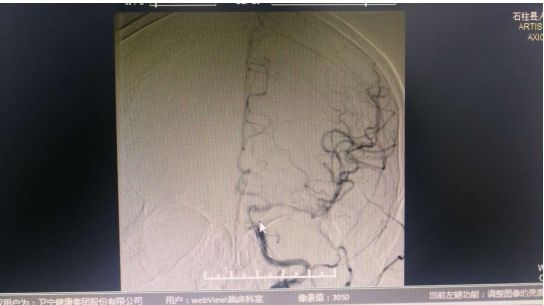

通过造影发现患者左侧颈内动脉闭塞 患者术后闭塞血管开通2020年3月13日,重医附二院石柱分院神经内科成功为一名急性脑梗患者实